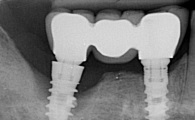

IMPLANTOLOGIE: LES IMPLANTS DANS LE SECTEUR ESTHÉTIQUE